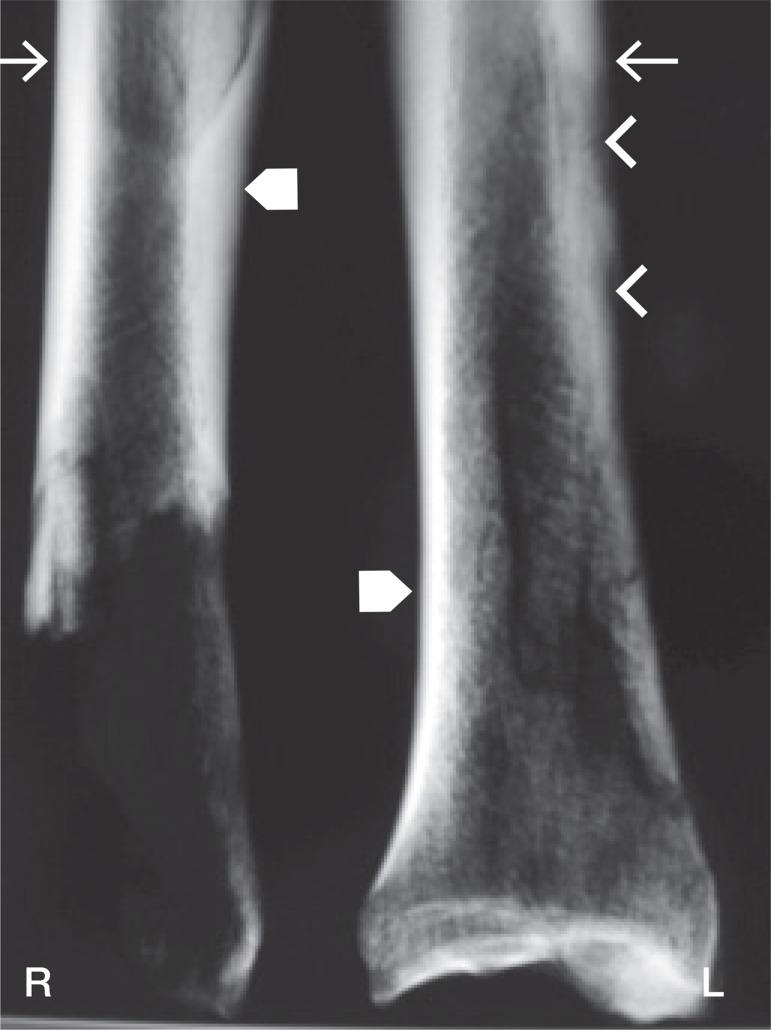

Medial tibial stress syndrome: a skeleton from medieval Rhodes demonstrates the appearance of the bone surface--a case report.